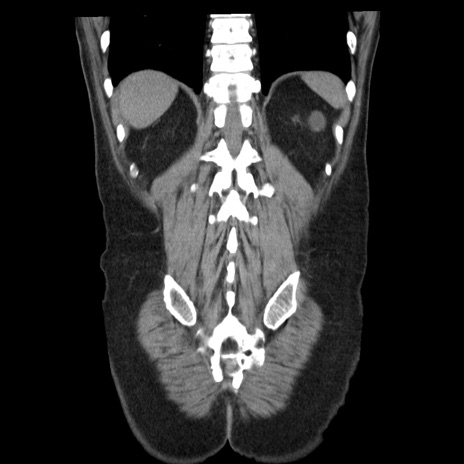

症例29(冠状断像)

【症例】40歳代男性

【現病歴】2日前から胃痛あり。徐々に周期的な激痛に変化した。本日になっても激痛があるため受診。

【身体所見】意識清明、BT 38-39℃台あり、腹部:膨満、やや硬、右下腹部に圧痛あり。

【データ】WBC 8500、CRP 23.26